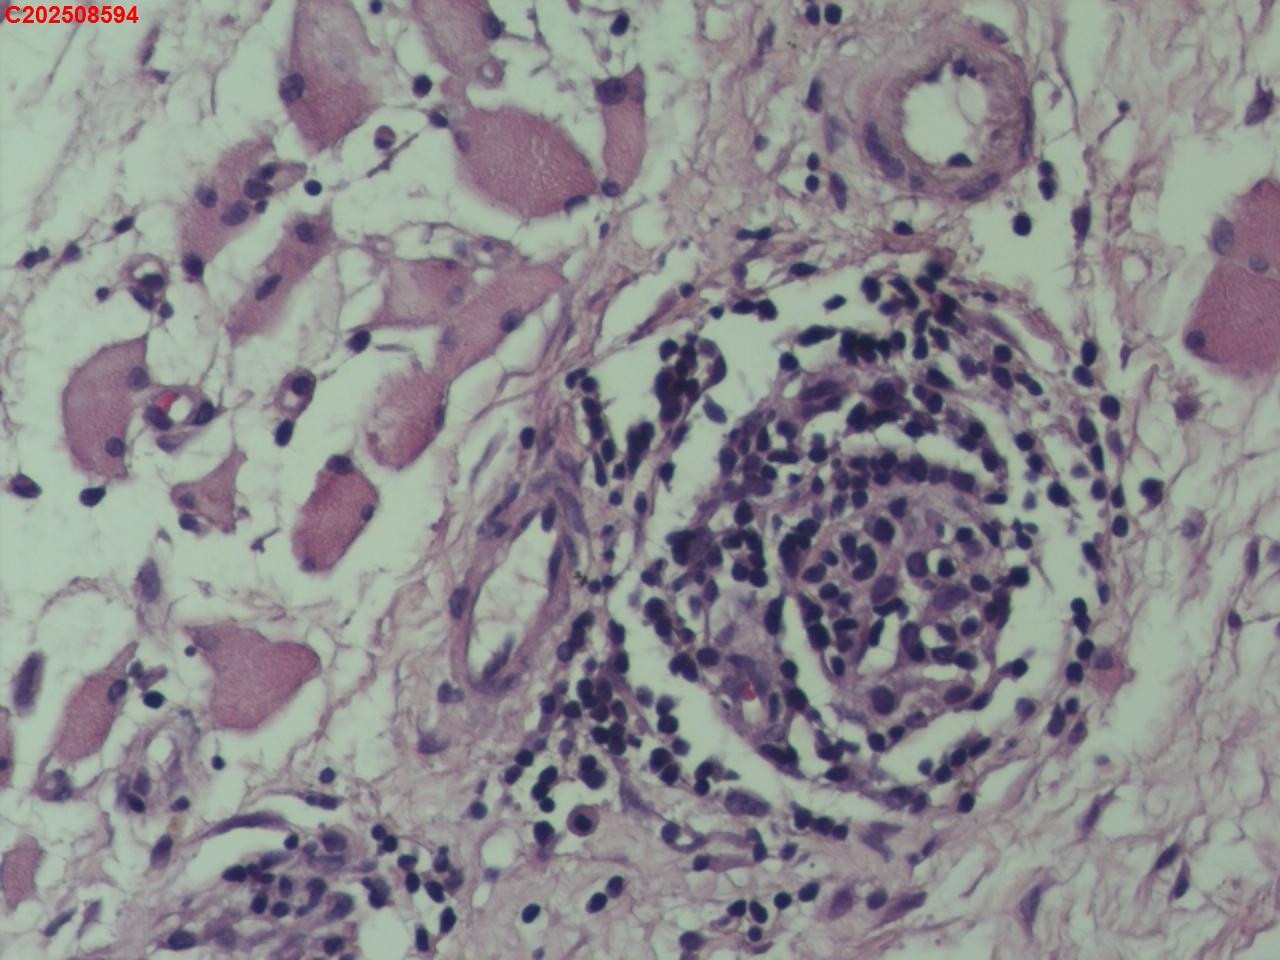

腰椎椎旁穿刺组织

性别年龄50岁临床诊断腰椎椎旁脓肿性质待查?

标本名称腰椎椎旁穿刺组织

大体所见腰椎椎旁穿刺组织2条

患者缘于入院前3个月无明显诱因出现腰腹痛,起初为隐痛,间断对症治疗,症状进行性加重,故入院前20天于某市第五医院就诊,查腰椎X片提示腰椎骨质增生,给予布洛芬、双氯芬酸钠等对症治疗,症状仍进行性加重,疼痛级别为5级,休息不能缓解,故入院前5天于某市第一人民医院就诊,查腰椎CT提示腰椎间盘膨出,腰椎退行性变,双侧腰大肌及背侧肌群增粗模糊致左侧输尿管下段粘连,尚短输尿管及肾盂扩张积水,腰背部皮下积液,嘱其回当地医院治疗,故入院前2天于某县中医院查彩超提示左侧腹腔内低回声包块,双肾积水、双侧输尿管上段扩张,右肾多发结石,遂于某市第二医院住院治疗,住院期间查CT提示双侧腰大肌及髂腰肌增厚、肿胀,左肾及输尿管腹段积水改变,腹膜后及左侧腹股沟区稍大淋巴结,左肺上叶及右肺中叶条索,胆囊多发结石子宫切除术后改变;血糖、肝肾功能、血脂基本正常,考虑腹腔结核可能。

描述诊断,未见结核病灶